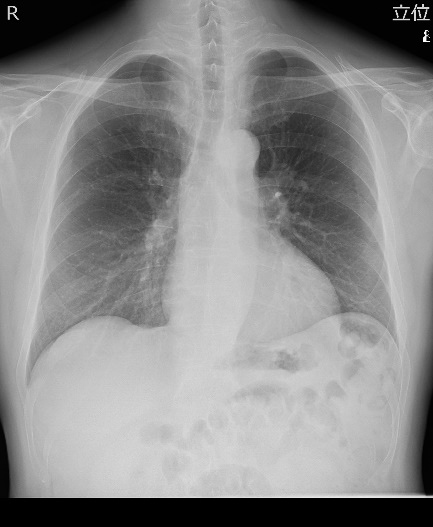

【一般撮影】

撮影部位にX線を照射し、その透過像を画像化する一般的なレントゲン検査のことです。当院では、「FPD(フラットパネルディスプレイ)システム」を導入しており、画像処理により迅速に高精度な画像を提供することができます。